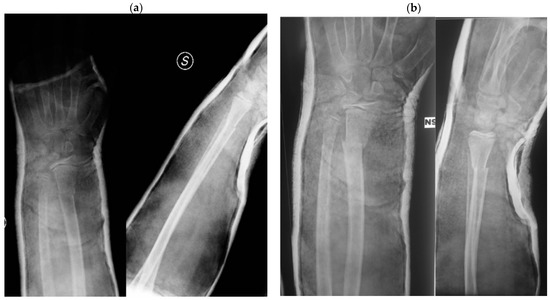

Both factors can interfere with proper fracture reduction, as the key components to achieve fracture stabilization with conservative treatment are proper cast molding, thin and uniform padding, and three-point fixation [13] (Figure 2).

Figure 2.

Case report of an obese patient. (a) Post-reduction casting X-ray; (b) one-week post-reduction X-ray with loss of reduction; (c) surgical treatment of the fracture.